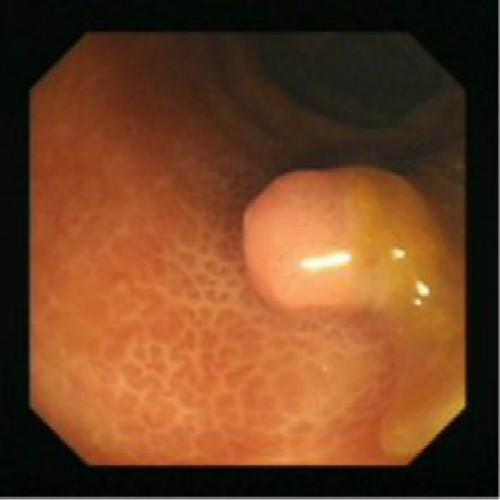

腫瘤性息肉

腫瘤性息肉圖的片